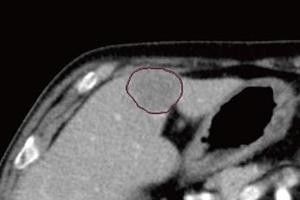

胸部X線CADサービス*6 |

肺結節検出サービス*7 |

肋骨骨折検出サービス*8 |

頭部高吸収/低吸収強調フィルタサービス*9 |

腹部吸収値強調フィルタサービス*10 |

*6 胸部X線CADサービス(CXR-AID)は,「胸部X線画像病変検出ソフトウェア CXR-AID」の【類型1】によって提供されるサービス。販売名:胸部X線画像病変検出(CAD)プログラム LU-AI689型 承認番号:30300BZX00188000

*7 肺結節検出サービスは,肺結節検出プログラム FS-AI688型で実現している。本サービスに含まれる肺結節性状分析機能は画像診断ワークステーション用プログラム FS-V686型,肺区域ラベル機能は画像処理プログラム FS-AI683型で実現している。

*8 肋骨骨折検出サービスは,肋骨骨折検出プログラム FS-AI691型で実現している。本サービスに含まれる肋骨ラベル機能は画像処理プログラム FS-AI683型で実現している。

*9 頭部高吸収/低吸収強調フィルタサービスは,画像処理プログラム FS-AI683型で実現している。

*10 腹部吸収値強調フィルタサービスは,画像診断ワークステーション用プログラム FS-V686型と画像処理プログラムFS-AI683型で実現している。